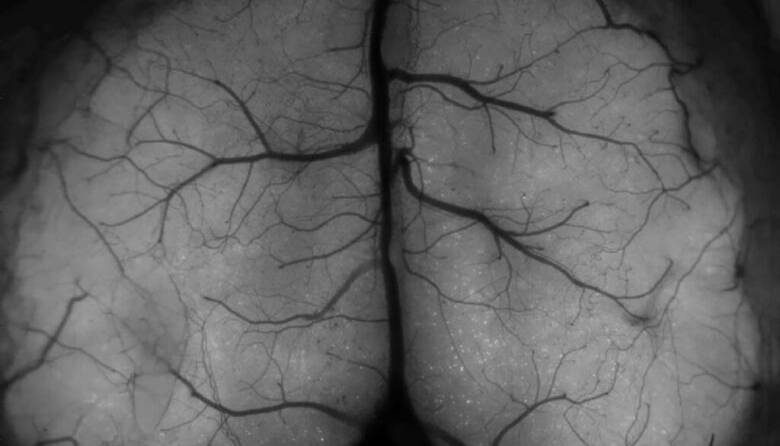

نحوه تشکیل خاطرات در مغز ثبت می شود

هر روز خاطرات جدیدی در مغز ما تشکیل و ذخیره می شود؛ اکنون محققان دانشگاه [...]